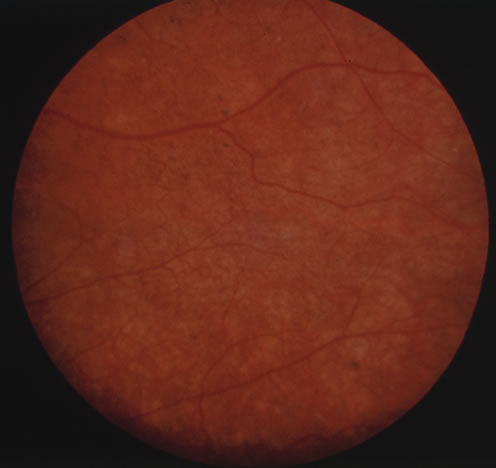

The acute retinal necrosis (ARN) syndrome is most often caused by the herpes zoster virus, although occasionally it may be a result of herpes simplex infection.12 It is typically described in healthy patients although association with immunosuppressed patients has also been described. Granular, nonhemorrhagic areas of retinal necrosis may be observed in the fundus, often rapidly coalescing with resulting blindness often caused by retinal detachment. There is often an associated vasculitis and vitritis. In immunocompromised patients VZV or HSV retinitis may also take the pattern of progressive outer retinal necrosis (PORN) (Fig. 6). PORN differs from ARN in that the former is multifocal, localized to the outer retina, and is less often associated with vasculitis and vitritis.